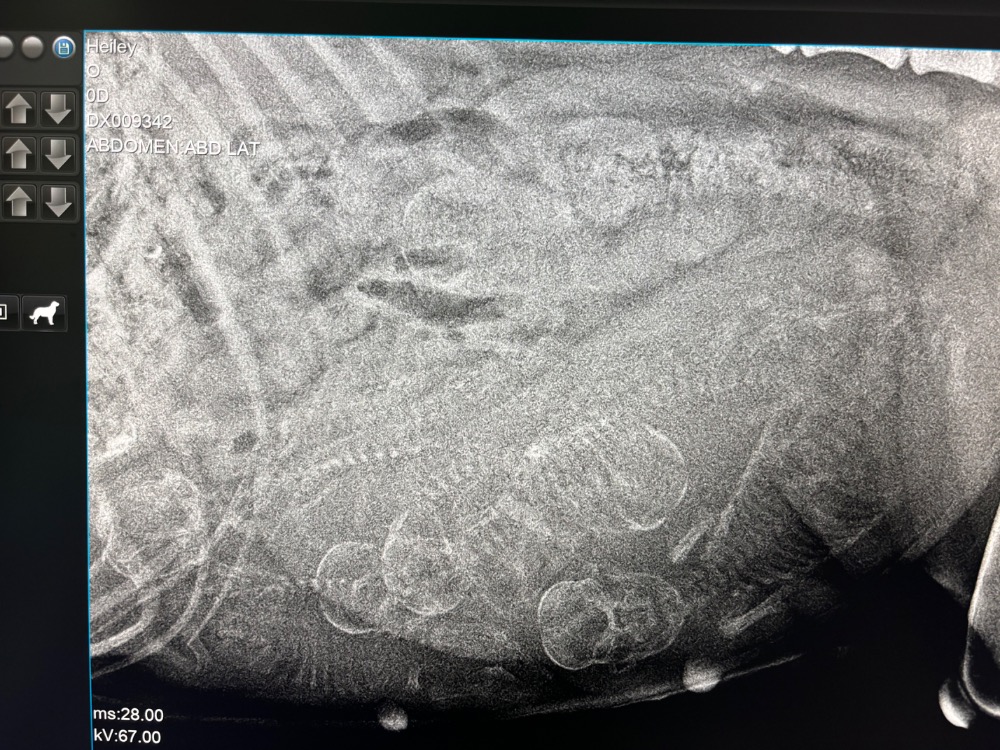

23.6.2025 jsme byli na kontrole u veterináře s Hailey a nechali jsme si štěňátka vyfotit, ať máme představu, kolik Holanďanů připlave :) Zkuste je spočítat a najít si to své štěně :D